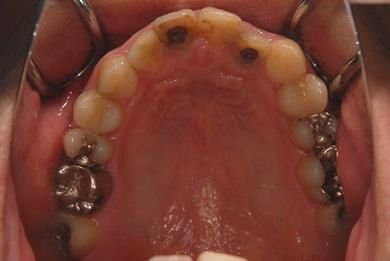

| 性別/年齢 | 男性 / 37歳 | ||||||||||||||||||||||||||||||||

| 主訴 | 数年前に神経を抜く治療をした下顎の歯が、1年ほど前にうずきを感じて治療をした際に、完全に治療するのは難しいと言われた。その歯がぐらつくように感じ始めたので、相談のために来院。 | ||||||||||||||||||||||||||||||||

| 治療内容 | インプラント1本(GBR)、メタルボンドセラミック1本 | ||||||||||||||||||||||||||||||||